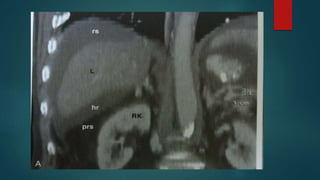

Hepatorenal space –morrisons pouch

 Just beneath the bare area the right

peritoneal space courses between the

posterior surface of segment 6 and the

anterior renal fascia .

 This is a relatively small potential space.

 It is the most dependent portion of the

right supramesocolic spaces